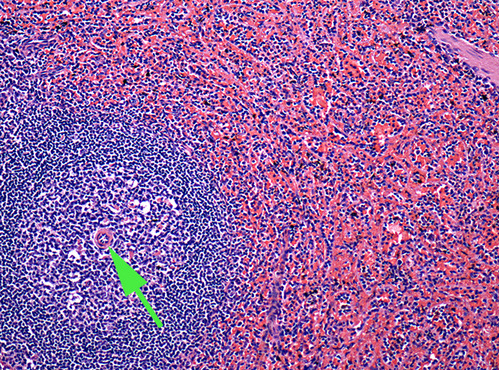

The artery at the end of the green arrow is the central artery of the spleen.

The dark area marked by the green arrow is

white pulp in the spleen.

The light area indicated by the green arrow is the

germinal center of a lymphatic nodule.